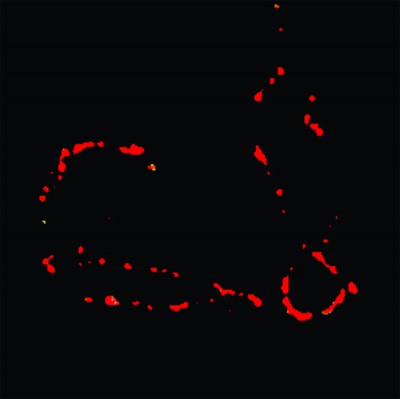

Científicos Argentinos desarrollan sensores fluorescentes para visualizar partículas nanométricas

Los científicos de la Facultad de Ciencias Exactas y Naturales de la UBA creen que, en el futuro, esta estrategia de microscopía podría usarse para la detección precoz del cáncer y otras enfermedades.

Imagen que...